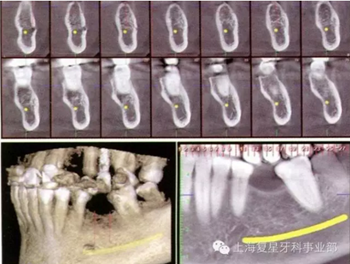

圖3a:左側(cè)下頜骨區(qū)CBCT掃描

一位55歲的健康女性,要求進(jìn)行下頜磨牙的修復(fù)。她的主訴是:左側(cè)下頜第一磨牙(36#牙)由于幾年前根管治療失敗而拔除導(dǎo)致磨牙缺失。經(jīng)過(guò)包括臨床和圖片分析的完整診斷評(píng)估后,使用ProMax(普蘭梅卡;圖1和3a)三維掃面儀對(duì)左邊的下頜骨進(jìn)行了CBCT掃描。